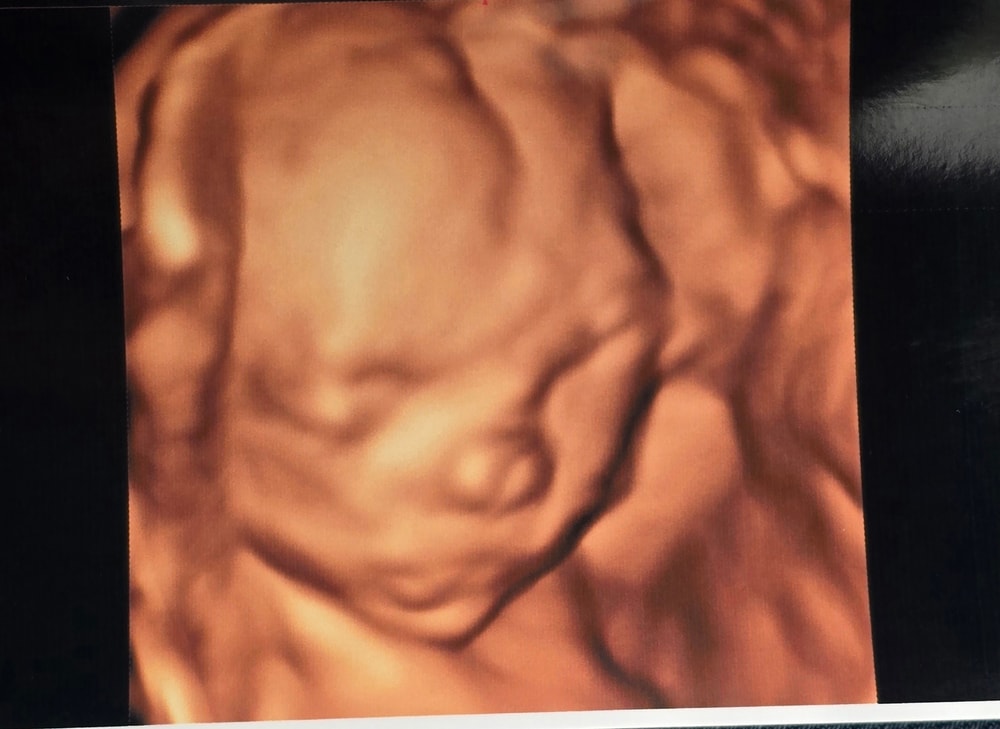

19 недель беременности 🩷3D узи

Даже сделали 3D УЗИ, может, рано еще, но пусть фотки будут. Сразу видно, нос папин. 😊 Лежит, машет ногами и руками, очень активная.